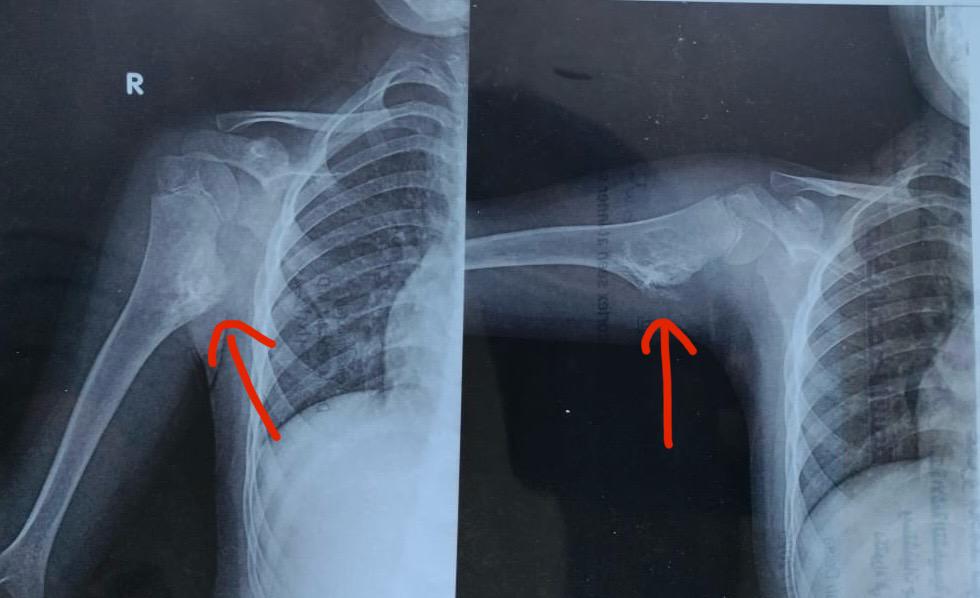

تحديد مكان الورم

الأشعة التشخيصية

قال الدكتور حسان النعمانى، رئيس جامعة سوهاج، إن فريق طبى وحدة جراحات اليد والجراحات الميكروسكوبية بالمستشفى الجامعى، نجح فى إجراء عملية جراحية دقيقة لطفلة تبلغ من العمر 10 سنوات، كانت تعانى من ورم ضاغط أعلى عظمة العضد، هدد ذراعها بمضاعفات خطيرة، أبرزها الغرغرينا نتيجة الضغط على الشريان الرئيسى المغذى للذراع، بالإضافة إلى تأثر الأعصاب الطرفية للضفيرة العصبية.

وأوضح الدكتور ياسر عثمان، مدير وحدة جراحات اليد والجراحات الميكروسكوبية، والذى قام بإجراء الجراحة، أن العملية تضمنت استكشافًا دقيقًا للضفيرة العصبية، مع عزل الأعصاب الطرفية عن الورم الذى كان ضاغطًا على الشريان والأعصاب، ثم تم استئصال الورم بنجاح، وخروج الطفلة من غرفة العمليات وهى فى حالة جيدة ومستقرة، مؤكدًا أن المتابعة مستمرة للاطمئنان على تحسن وظائف الذراع بشكل كامل.